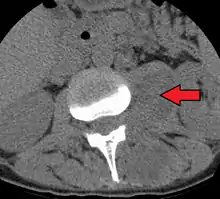

An abscess in the psoas muscle of the abdomen may be caused by lumbar tuberculosis. Owing to the proximal attachments of the iliopsoas, such an abscess may drain inferiorly into the upper medial thigh and present as a swelling in the region. The sheath of the muscle arises from the lumbar vertebrae and the intervertebral discs between the vertebrae. The disc is more susceptible to infection, from tuberculosis and Salmonella discitis. The infection can spread into the psoas muscle sheath.[1]

Paraspinal abscess in the psoas muscle